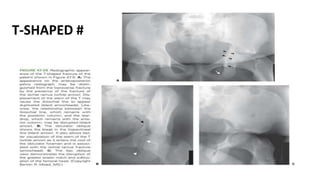

This document discusses different types of acetabular fractures including transverse, T-shaped, and both-column fractures. Transverse fractures are classified as transtectal, juxtatectal, or infratectal based on their location through the acetabular dome or fossa. Transtectal fractures require anatomical reduction while infratectal fractures may not need surgery depending on the pattern. T-shaped fractures disrupt the obturator ring and iliopectineal and ilioischial lines but do not involve the iliac wing, differentiating them from both-column fractures. CT scans can further classify fractures in the coronal or sagittal planes.